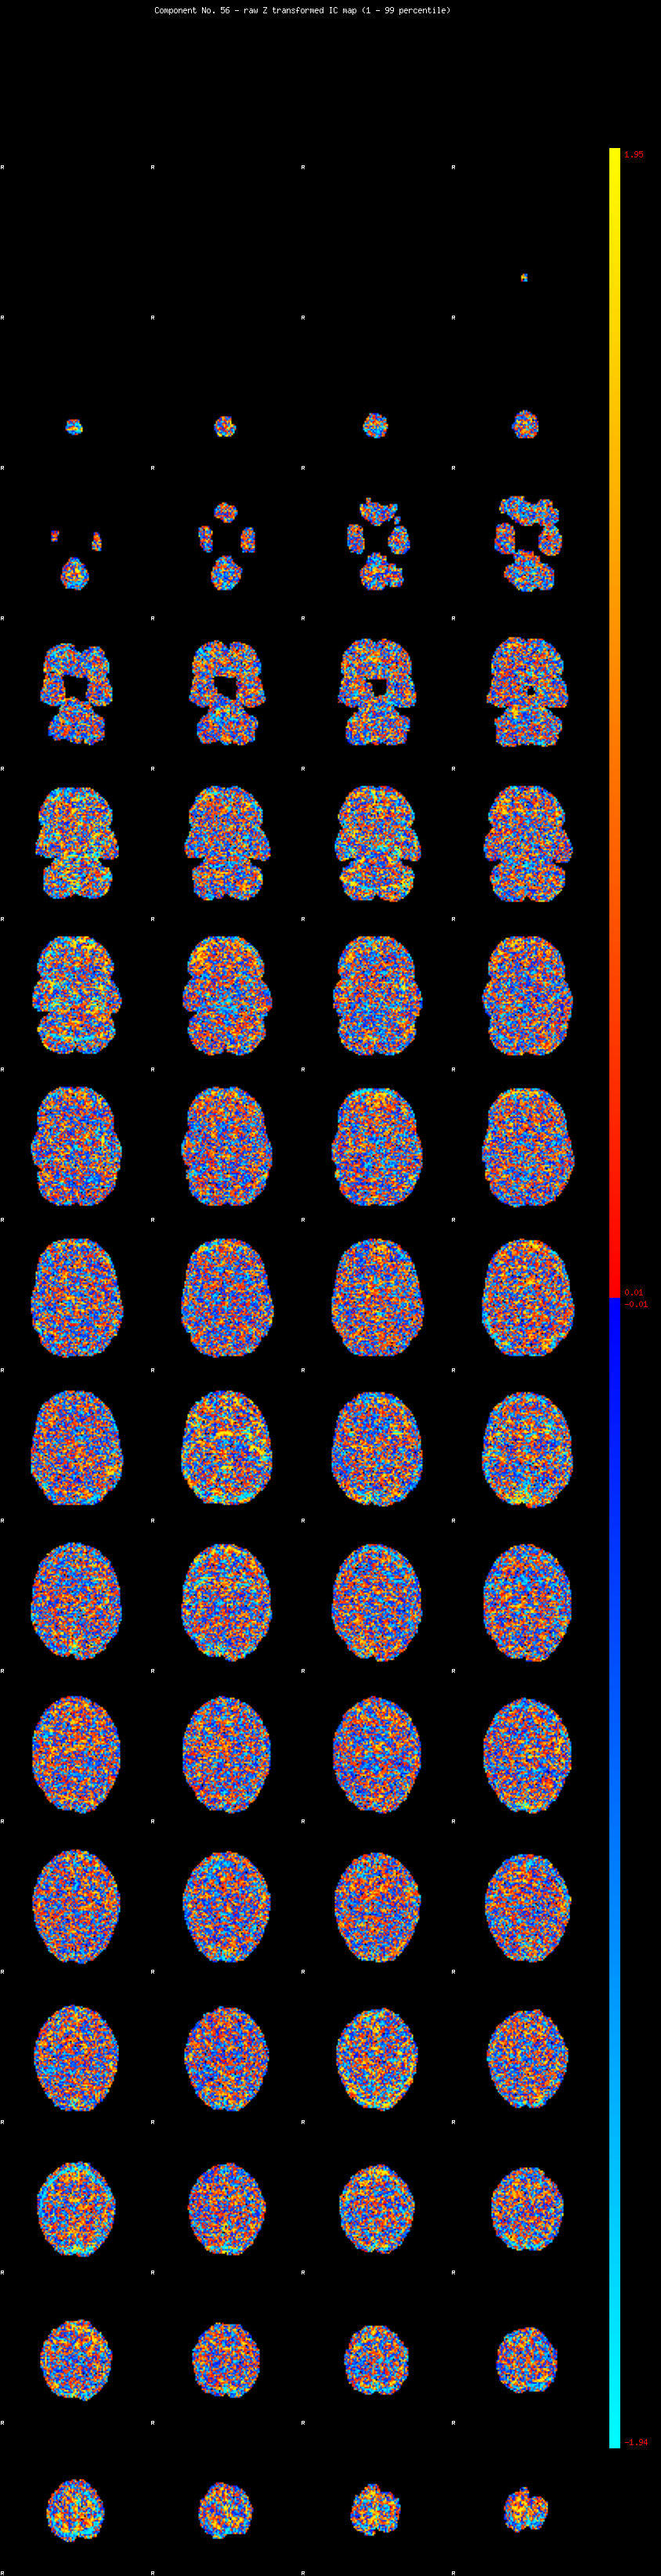

IC_56 Mixture Model fit

Means : -0.000000 2.095913 -2.055620

Vars : 1.000000 0.895439 0.793458

Prop. : 0.930974 0.033610 0.035416